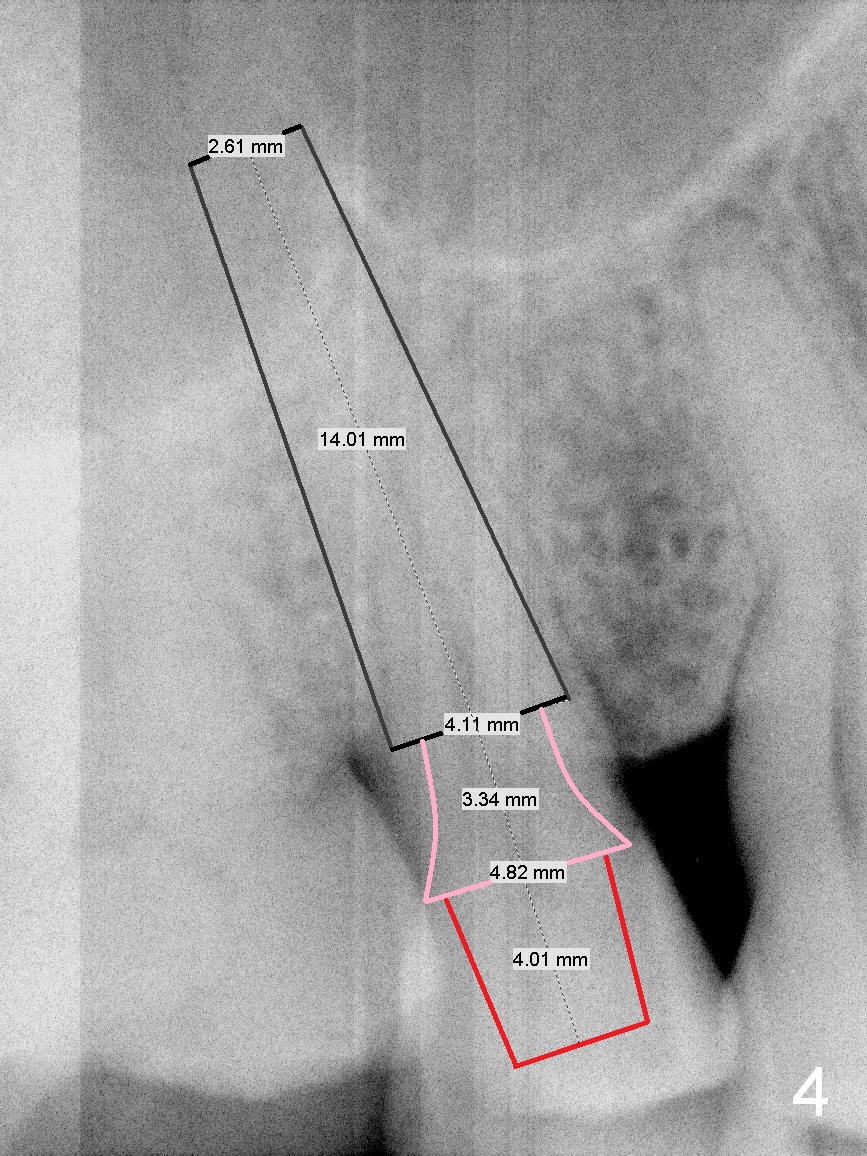

A 61-year-old man (WJ) cracked the tooth #31 after RCT. Four years after #31 extraction, the tooth #4 cracks by itself. The apex of the tooth appears to protrude into the sinus and is closely associated with the sinus septum (triangle: Fig.2,3). An implant will reach the top of the socket for stability (Fig.4 black area). The abutment is expected to be 4.8x4(3) (SM) or 4.5x4(3) (UF) mm. Metronidazole will be used for disinfection of the socket. On returning, he requests #31 implant.